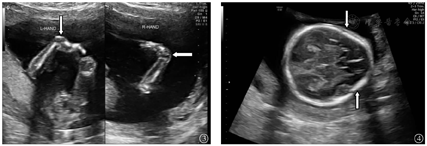

本组175例中孕期18-TS胎儿最常见超声结构异常(心脏、肢体、面部畸形及中枢神经系统异常)胎儿中,心脏畸形以室间隔缺损最为常见(70例、40.0%),其次为心内膜垫缺损(28例、16.0%)(图2);肢体畸形以钩状手(第3、4指紧贴手掌,第2、5指压在其上)最为常见(35例、20.0%)(图3),其次为重叠指(28例、16.0%);面部畸形以小下颌(43例、24.6%)最为常见;中枢神经系统异常以草莓头(33例、18.9%)(图4)最为常见。本组175例中孕期18-TS胎儿最常见超声结构异常心脏、肢体、面部畸形及中枢神经系统异常分布情况,见表2。

18-TS胎儿多伴有解剖结构异常,并且表现为多发畸形[19]。本组175例中孕期18-TS胎儿超声检查结果显示,157例(89.7%)异常≥2项,最常见为心脏畸形(131例、74.9%),心脏畸形中又以室间隔缺损最为常见(70例、40.0%),其他特征性表现包括钩状手(35例、20.0%),小下颌(43例、24.6%),草莓头(33例、18.9%)。虽然18-TS胎儿四肢畸形较常见,但是受胎儿体位、羊水、产前超声检查医师经验不足等限制,中孕期超声检查对该类畸形漏诊率较高[24]。因此,中孕期超声检查发现胎儿存在其他部位畸形时,更应重点观察其肢体,发现草莓头、小下颌、钩状手、脉络膜囊肿、心脏畸形等特征性超声异常及多发异常时,应高度警惕18-TS。对于中孕期超声检查发现异常≥2项的胎儿,建议对其进行遗传学咨询,必要时进行染色体核型分析。

越来越多研究发现超声软指标异常,即微小异常指标,在胎儿结构发育检测方面有独特应用价值[25]。本组175例18-TS胎儿中,最常见超声软指标异常为脉络丛囊肿(116例、66.3%),仅次于心脏畸形,这与Cheng等[26]研究结果一致。正常妊娠胎儿脉络丛囊肿发生率为1%~2.5%,一般于胎龄>22周时,该症状可逐渐消失,若动态观察至胎龄为26周时,该症状仍未消失,或合并其他超声软指标异常,应对此类胎儿进行产前诊断[27,28]。因此,若中孕期超声检查发现胎儿脉络膜囊肿,临床应提高警惕,详细筛查胎儿其他结构,尤其注意是否合并心脏畸形与肢体畸形。中孕期超声检查和辨识超声特征,可提高18-TS高风险胎儿检出率,避免不必要的有创检查,降低18-TS胎儿出生率[1,29,30]。